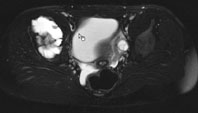

Ein 13-jähriges Mädchen kommt humpelnd zu Ihnen in die Praxis mit Schmerzen in der rechten Hüfte, die seit einigen Monaten bestehen und besonders bei Belastungen auftreten. Eine sichtbare Schwellung besteht nicht, kein Sturzgeschehen in der Anamnese.

Die Röntgenuntersuchung von Becken/Hüfte zeigt eine septierte geographische Osteolyse in der Ala und im Korpus des Os Iliums rechts. Das Röntgenbild und die Aufnahmen der nachfolgenden MRI-Untersuchung sehen Sie hier:

T2 FS, axial, 5 mm

Bild vergrössern

T1 FS, axial, 5 mm